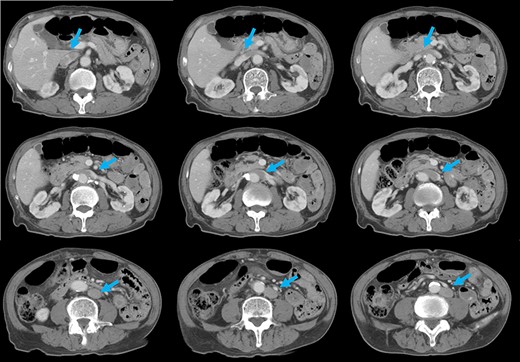

Preoperative computed tomography (CT) revealed a tumor in the sigmoid colon accompanied by some regional lymph node swelling (Fig. 1). It also showed that the IVC ascended vertically along the left side of the abdominal aorta. After connecting with the left renal veins, the left-sided IVC crossed the abdominal aorta anteriorly to join the normal prehepatic segment of the IVC (Figs 2 and 3). Coronal CT showed that the descending colon misplaced at the abdominal midline and the sigmoid colon in the right upper abdomen (Fig. 4). The preoperative diagnosis was thus sigmoid colon cancer with left-sided IVC and PDM.

After coronal reformation, the CT images show that the descending colon was at the midline of the abdomen (arrowheads), and the sigmoid colon was in the right upper abdomen (arrows).

PDM is a developmental anomaly characterized by failure of the descending mesocolon mesentery to fuse with the posterolateral parietal peritoneum [2]. The non-fused mesentery is then responsible for considerable variations in the position of the descending mesocolon. In our case, the descending colon was at the abdominal midline, and the sigmoid colon was in the right upper abdomen. Coronal reformatted images obtained by multidetector CT (MDCT) proved useful for an accurate preoperative diagnosis of the malpositioned descending colon. It is widely accepted that MDCT is an effective technique for staging colon cancer preoperatively [10]. MDCT also allowed us to generate multiplanar coronal images, which depicted the location of the colon as it would appear during the surgery. Moreover, MDCT angiography can be used to evaluate the running direction of the vessels. Because it has been reported that the left colon and sigmoid colon arteries and the superior rectal artery often branch radially from the inferior mesenteric artery, and that a marginal vessel may run abnormally due to the unusual mesenteric adhesion [5], accurate evaluation of the arteries is important for safe lymph node dissection.